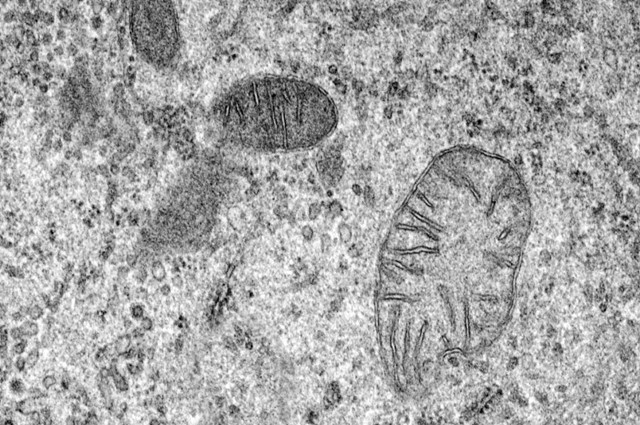

金相學(xué)是對(duì)合金微觀結(jié)構(gòu)的研究:相,夾雜物和其他成分的微觀尺度空間分布。各種技術(shù)(通常是顯微技術(shù))可用于揭示合金的微觀結(jié)構(gòu)。